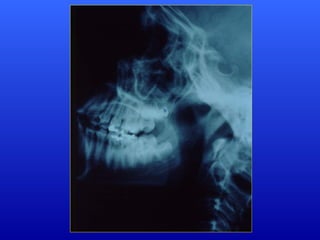

Respirador Misto: apresentaalternância de permeabilidade da via aérea e obstrução nasal, conferindo-lhe características próprias. Retrognatismo discreto com relação aceitável entre as arcadas; Palato ogival; Alongamento e protusão da arcada dentária superior; Lábio superior alongado; Nariz curto.